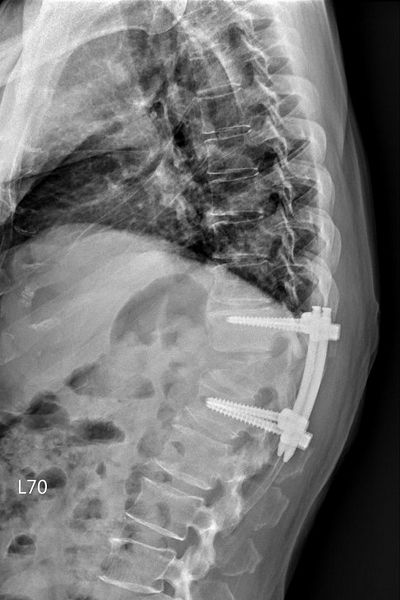

神經管受壓迫須進行良好的減壓,才可以讓神經學症狀達到改善,以邱先生為例,醫師在術中除給予良好的減壓外,還進行微創釘固定,幫助穩定脊椎。「減壓及微創釘手術」首先需要將脊椎後側的椎板切除進行完整減壓後移除部分腫瘤,並透過術中X光檢查確認位置,將4根微創骨釘分別固定在胸椎第11節及腰椎第1節,最後再以金屬桿連接兩端,不需破壞很多肌肉層即可達到穩定脊椎的作用。而過去手術通常使用的是傳統骨釘,術中需要劃一20公分的傷口,分離背部肌肉後將8根傳統釘固定於病灶上下各兩節脊椎處。洪立偉醫師指出:「微創釘的優點在於病人可以免於大傷口的疼痛,不用破壞很多肌肉就可維持脊椎穩定。此外,相較於傳統釘,微創釘的使用也能夠降低病人之後鄰近脊椎節出現退化而需再次進行手術的機率。」